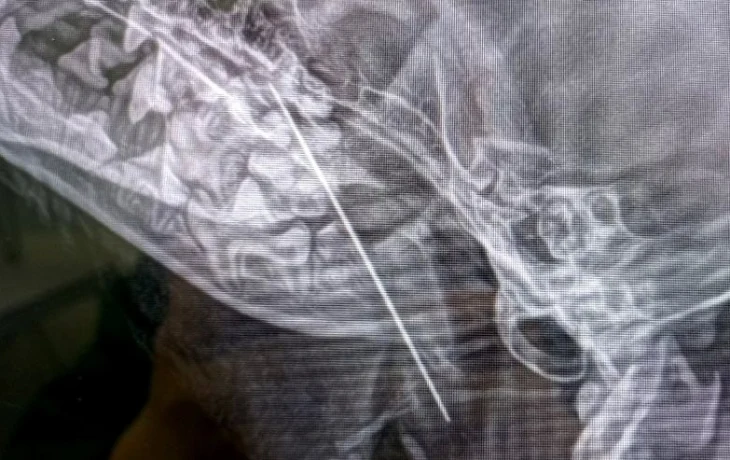

Собаку привезли в клинику с жалобами на кашель. Незадолго до этого Маруся стащила с хозяйской кухни кусок форели и съела его. Сначала хозяева предположили, что она подавилась рыбной костью. Однако врачи сделали щенку рентген и выяснили, что в мягких тканях его глотки застряла игла. Пушистую пациентку отправили на экстренную операцию, в ходе которой хирург Наталья Польдяева успешно извлекала инородный предмет.

Фото: пресс-служба Мосветобъединения